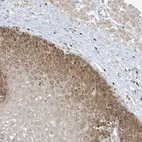

Immunohistochemical staining of human esophagus shows moderate cytoplasmic and nucleolar positivity in squamous epithelial cells.